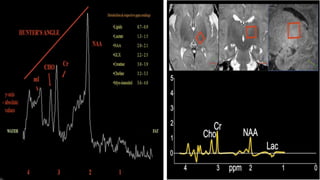

2. Proton Magnetic Resonance spectroscopy(MRS)

BRAIN IMAGING MODALITIES:- •CRANIAL SONOGRAPHY :- can demonstrate edema as loss of gray-white differentiation and small ventricles when severe but is generally insensitive for detection of HI injury. • CT :- used to detect cerebral edema , hemorrhage and eventually HI brain injury. • MRI :- Best imaging modality for determining the presence , severity & distribution of irreversible HI brain injury. 1. Diffusion – weighted imaging (DWI) – Early DWI –usually show restricted diffusion in areas affected by hypoxic- ischemia At 7 to 10 days – pseudonormalisation of diffusion After 7 to 10 days - diffusion usually increased in areas of affected areas 2. Proton Magnetic Resonance spectroscopy(MRS) 3. Susceptibility – weighted imaging 4.Magnetic Resonance Angiography or Venography